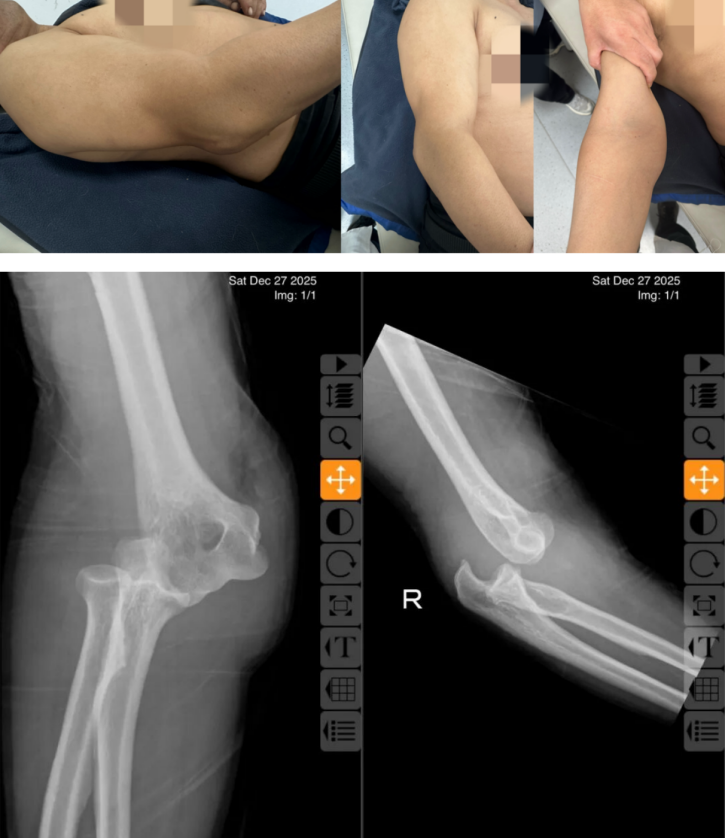

据了解,王先生因不慎摔倒导致右肘部严重受伤,当即感到剧痛,关节迅速肿胀畸形,活动受限。事发一小时内,在家属搀扶下赶往西安红会医院就诊,此时,伤处已高度肿胀,主动与被动活动完全受限,情况危急。接诊医师薛安邦迅速完成初步查体,结合DR影像,判断为右肘关节后脱位,随即联系手法复位室董博主任与周健副主任医师。团队凭借丰富经验快速确诊,并决定立即施行手法复位。“肘关节后脱位若延误治疗,可能加重肌肉痉挛、压迫血管神经,甚至引发前臂缺血性肌挛缩等不可逆损伤。”董博主任细致向家属讲解病情与治疗方案,同时温和安抚王先生,“你放心,我们会尽量减轻你的痛苦,争取一次复位成功。”三位医护人员沉稳专业的态度,让患者与家属悬着的心渐渐落地。

由于王先生肘部肿胀严重、疼痛剧烈,给复位操作增加了不小难度。薛安邦医生先为患者摆放好舒适体位,为复位顺利开展筑牢基础。复位过程中,董博主任稳健施力牵引,周健主任精准固定配合,薛安邦医生则从旁安抚引导。随着一声标志复位的“咔嗒”轻响,肘关节成功归位,王先生的疼痛即刻大幅缓解,手臂恢复部分活动能力。复查DR影像显示,肘关节已完全复位,关节间隙恢复正常。随后,薛医生为患者完成石膏固定,并详细交代复位后注意事项。